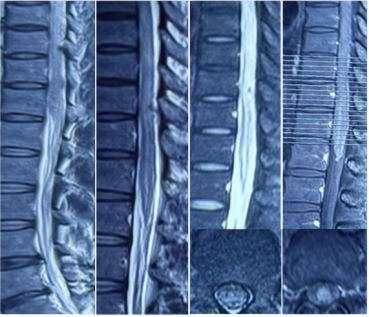

2024年4月,患者无诱因出现双下肢无力,尚可行走,上楼梯费力。2024年7月27日,患者晨起后发现双下肢无力加重(2天内加重到2级),伴下肢麻木,尿便障碍;胸腰椎增强磁共振成像(MRI)示胸腰段脊髓弥漫性病变伴强化(图1);腰穿脑脊液压力150 mmH2O,白细胞9*106/L,糖4.7 mmol/L,氯化物126 mmol/L,蛋白0.47 g/L,寡克隆区带(OB)阴性;血抗水通道蛋白4(AQP4)、髓鞘少突胶质细胞糖蛋白(MOG)、胶质纤维酸性蛋白(GFAP)-IgG(-);血肿瘤标志物、抗核抗体(ANA)、布氏杆菌凝集试验(-);诊断脊髓炎,予以静脉滴注甲泼尼龙1 g qd*3 d→500 mg qd*3 d→240 mg qd*3 d→序贯口服甲泼尼龙60 mg qd 每周减1片,出院时双下肢基本无法活动。经过康复锻炼,2024年8月,患者双下肢可抬离床面,自觉麻木平面下降,有尿意,间断导尿。

图1 胸腰髓增强MRI

第一阶段病程:患者亚急性起病,病初为双下肢无力,3个月期间无明显变化,3个月后突然急性加重,不符合急性脊髓炎的病程特点,结合下胸段脊髓长节段长T2信号、水肿明显、脊髓可见可疑的血管流空影,需考虑脊髓血管病。进一步完善颈胸腰椎增强MRI,可见胸髓多发斑片状异常信号、脊膜不均匀增厚伴强化、脊髓周围多发迂曲血管影、脊髓表面含铁血黄素沉积(图6)。脊髓数字减影血管造影(DSA)可见左侧T10肋间动脉造影时早期静脉充盈、迂曲扩张,考虑为硬脊膜动静脉瘘(SDAVF)可能大(图7)。治疗方面,于神经外科行硬脊膜动静脉瘘切除术。

图6 胸髓增强MRI